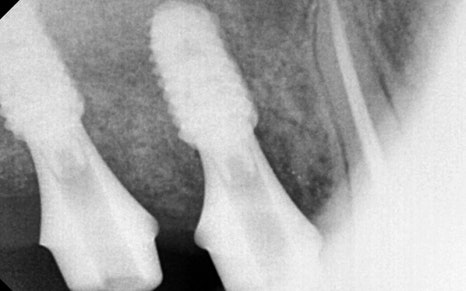

✅ Successful maxillary sinus lift & implant placement

and at the same time placed the implant

in a clear, precise position.

Seoul Of Dental Hospital always follows the principle of placing implants

parallel to the opposing teeth

and in a position where they occlude properly.

At the one-month check after placement,

we confirmed that there were no particular issues,

and decided to wait while the implant integrated well with the jawbone.